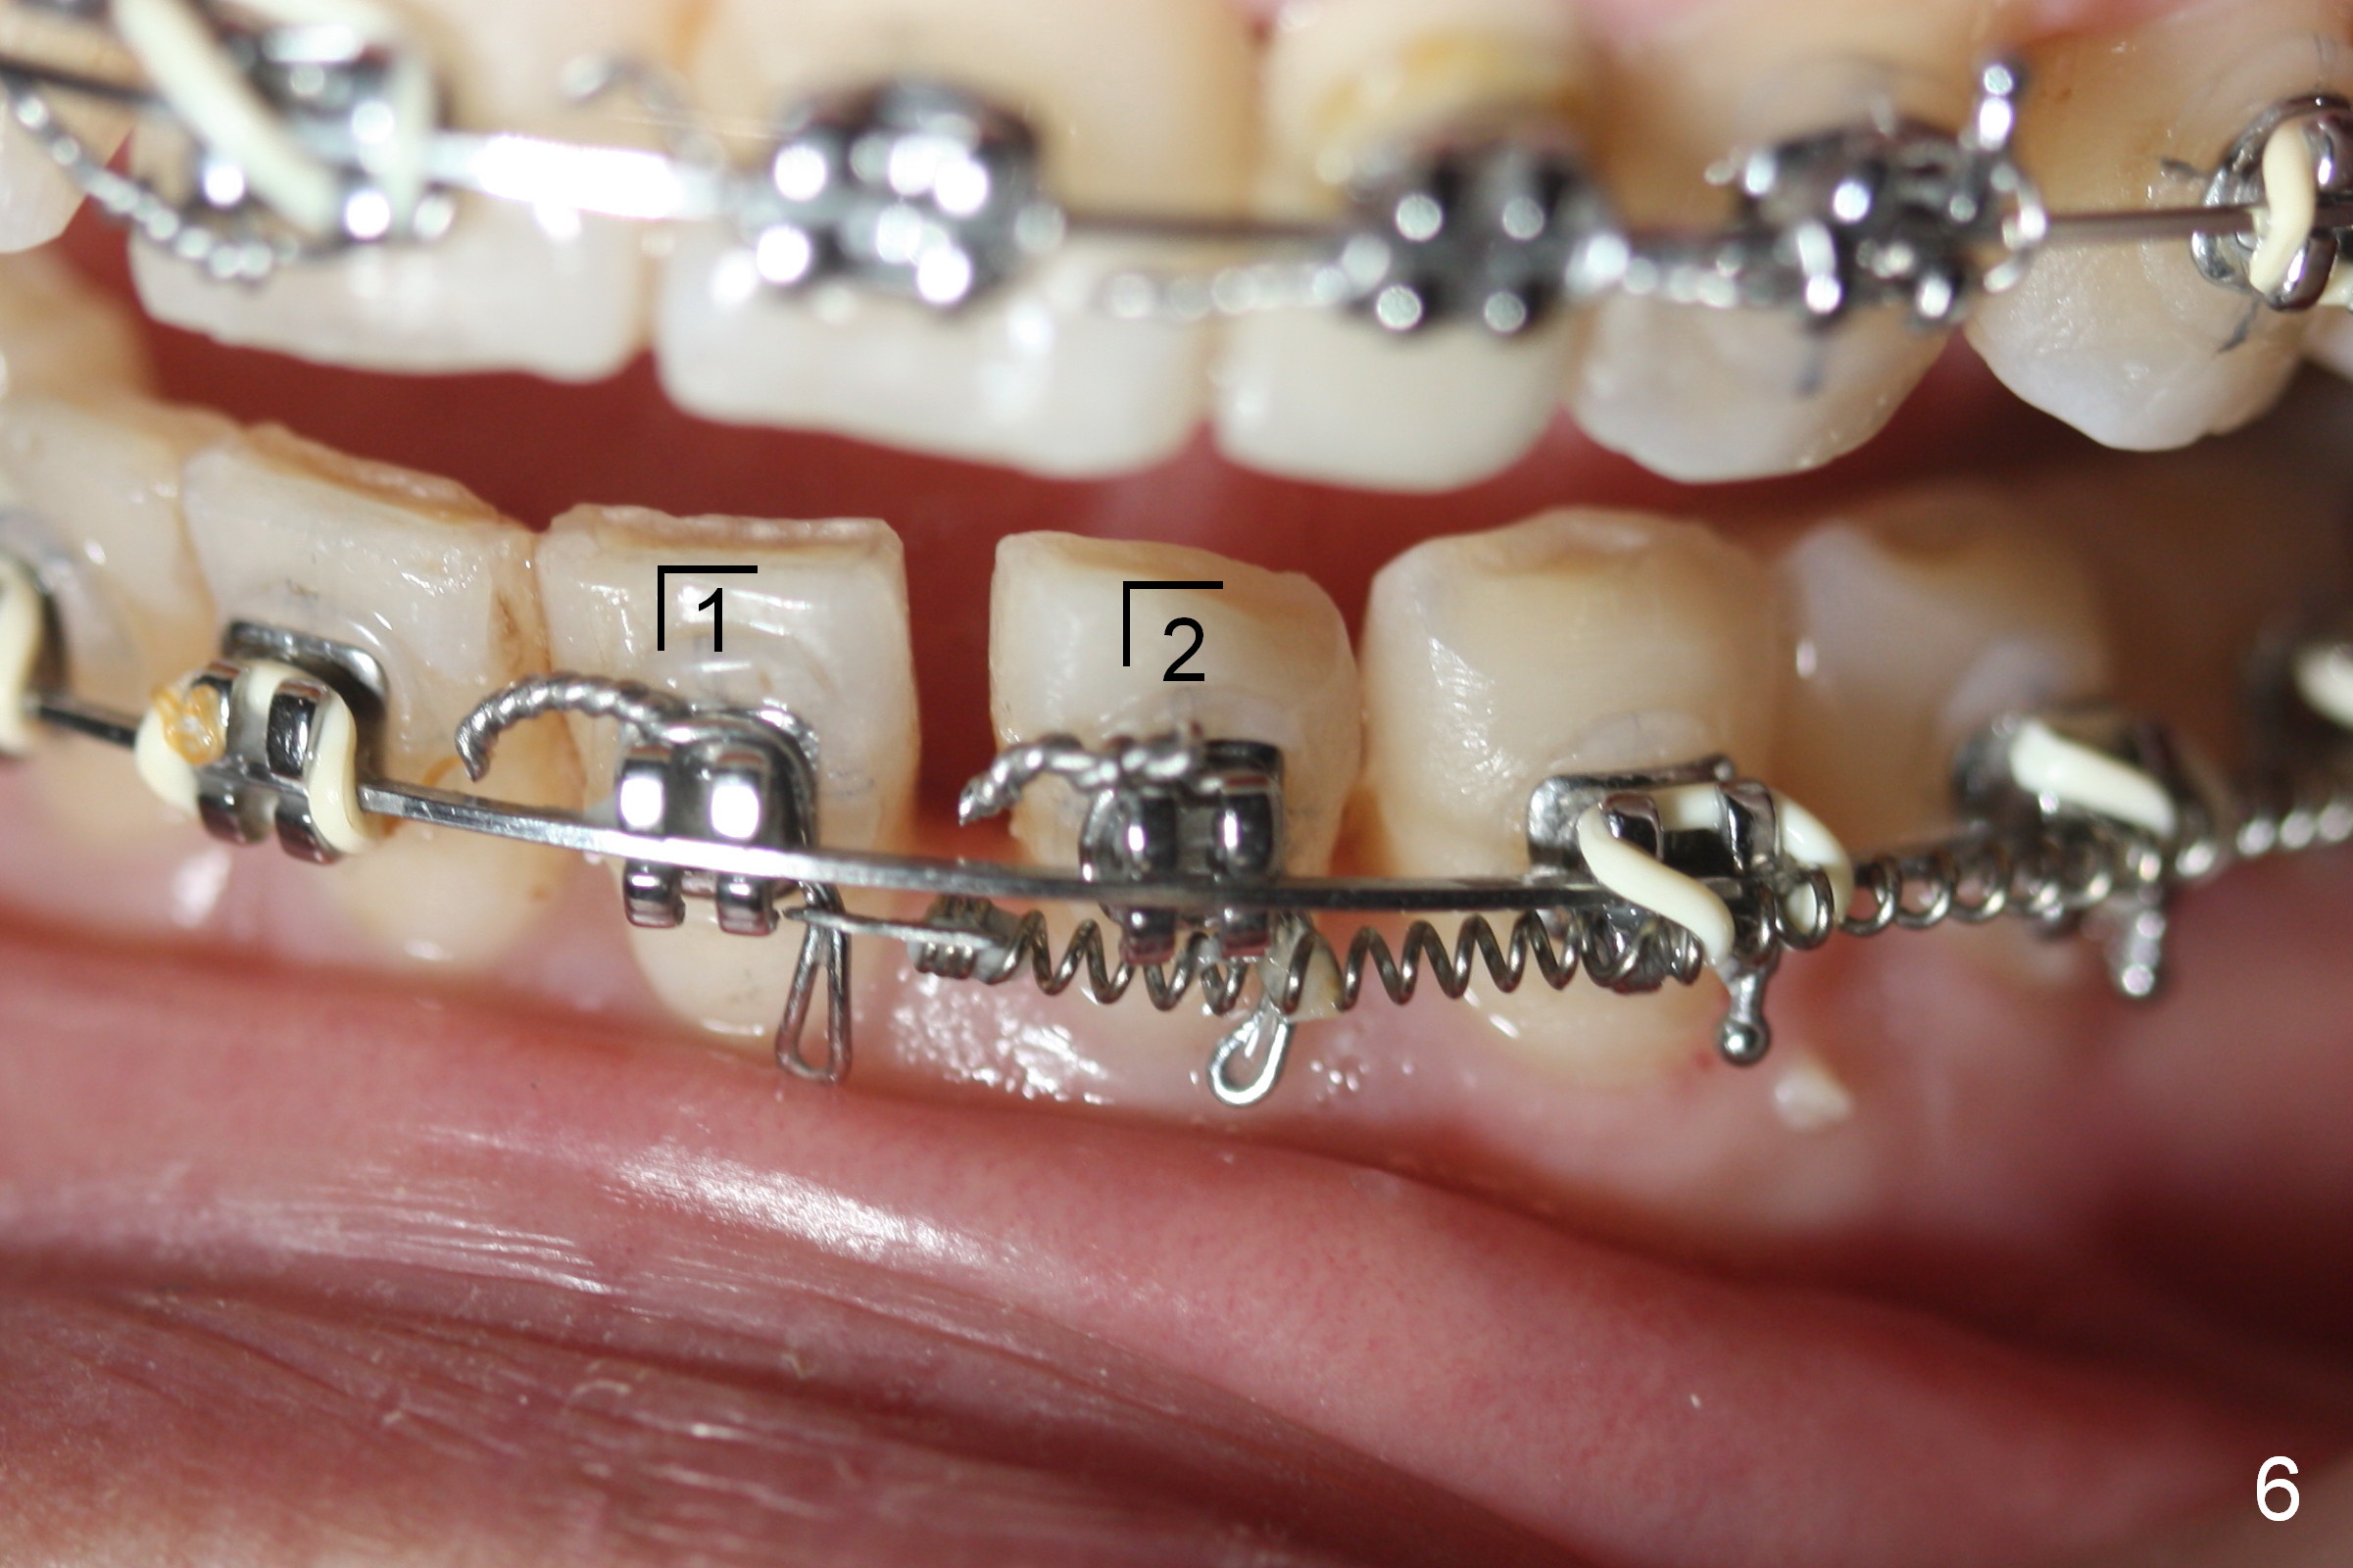

What has been done is arch wire sequence, proximal reduction and move the upper right teeth to the right (Fig.5) and the lower left teeth to the left (Fig.6) sequentially. It may be not enough when the unilateral Class II malocclusion is not addressed directly. Pay attention to the present occlusion now and address properly.